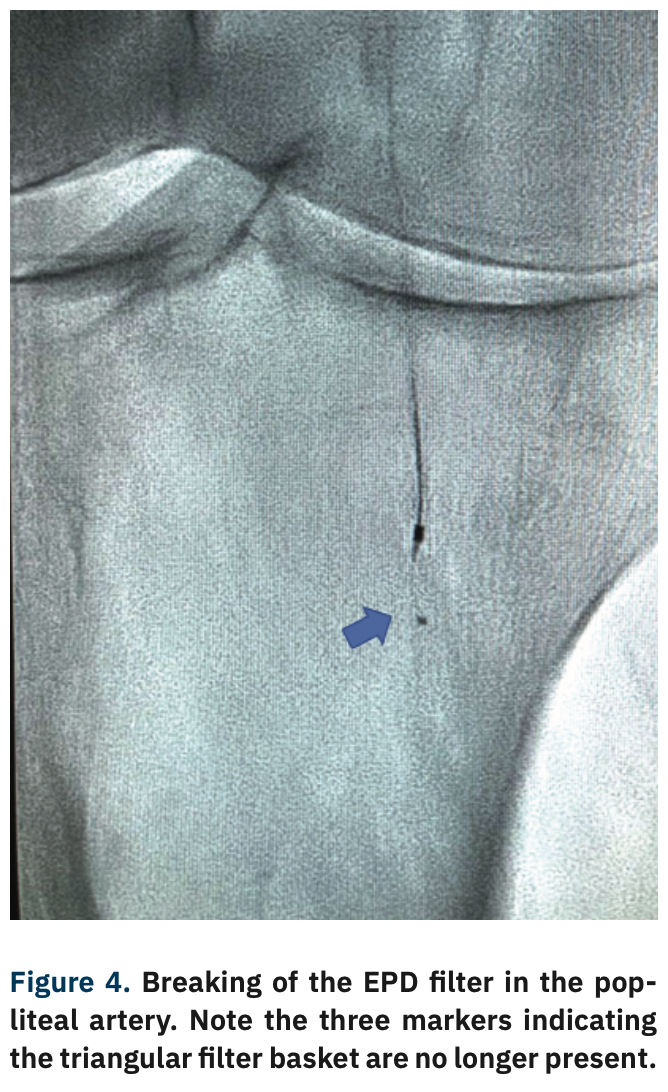

A complication occurred when removing the EPD filter when the tip broke into the popliteal artery, requiring removal (Figure 4). The Goose Neck loop snare (Medtronic) technique was used to effectively remove the two broken filter pieces (Figure 5). Following removal, final angiogram pictures were obtained, and demonstrated no dissection or perforation of the vessels (Figure 6). The distal SFA and popliteal artery occlusions resolved from 90% stenosis to <20% residual stenosis.